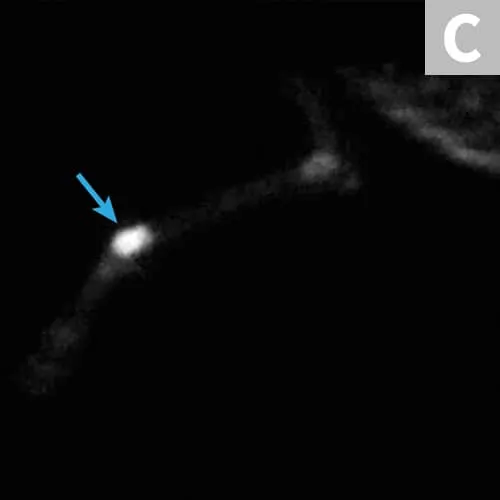

In other cases for which the morbidity of surgery is high or the MCT has gross characteristics of malignancy (eg, large size, ulceration, firm adherence to underlying tissues), full staging should be considered before surgical removal. High-grade MCTs should be fully staged. Wide excision is the recommended therapy for MCTs (Figure 3). Surgical treatment is the mainstay of MCT treatment, but adjuvant chemotherapy may be indicated in high-grade tumors and cases with evidence of metastasis. Adjuvant radiation therapy may be indicated in cases in which local control cannot be achieved with surgery alone.

(A) MCT over thorax, planned wide resection (B) Specimen after wide resection. The specimen will be inked on the radial and deep margin for tumor-margin assessment.